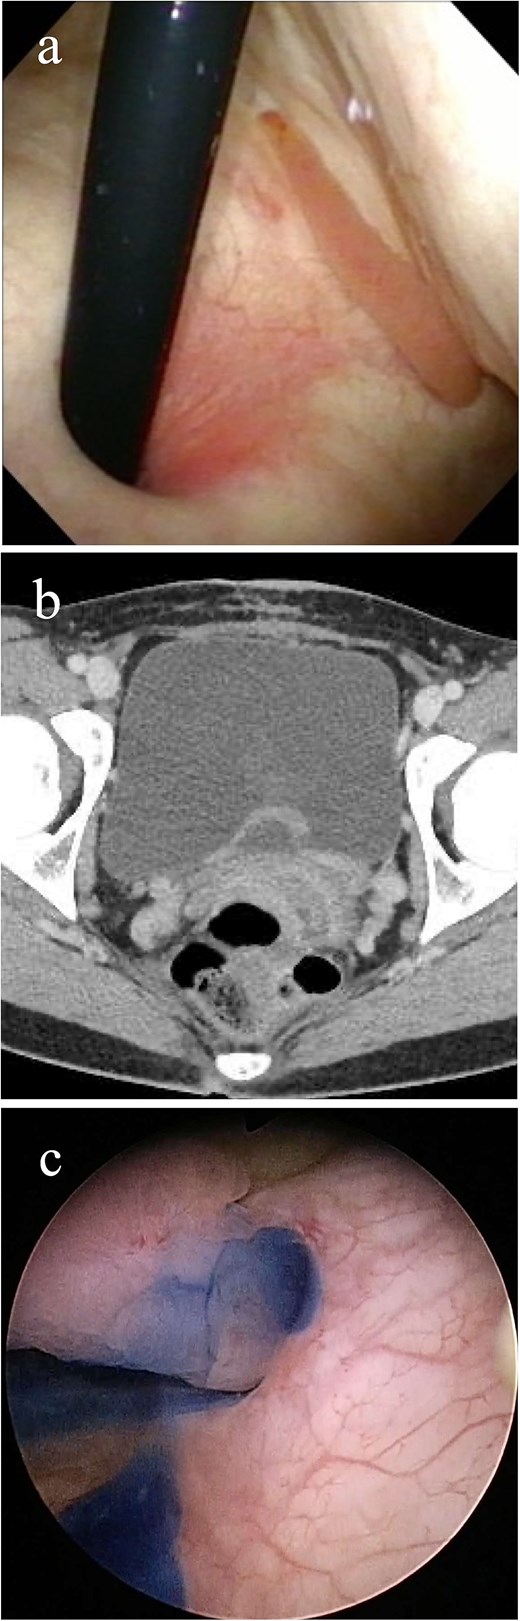

A 32-year-old Japanese woman presented to our hospital with painless intermittent gross hematuria that had persisted for 5 months. She had no history of urolithiasis or urinary tract infections. Her blood test results were within normal limits. Although urine analysis revealed microscopic hematuria, urine culture, and cytology tests were negative. Cystoscopy performed in the outpatient clinic revealed a smooth-surfaced snake-like tumor protruding from the left ureteral orifice into the bladder lumen, moving like snake’s crawling with respiratory movements (Fig. 1a). Contrast-enhanced computed tomography (CT) revealed a 3-cm-long soft tissue shadow around the left ureteral orifice (Fig. 1b). Urolithiasis or hydronephrosis was not observed.

Imaging study findings. (a) Cystoscopy finding. Cystoscopy revealed that a tumor protruded from the left ureteral orifice into the bladder lumen, showing serpentine locomotion with respiratory movements. (b) Contrast enhanced computed tomography finding. Soft tissue shadow was detected around the left ureteral orifice, revealing a long thin tumor. (c) Indigo carmine was excreted through the left orifice that is occupied by the tumor.